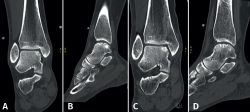

Lesions can be characterized by location, morphology, and size. Location can be described using a 9-grid anatomical scheme of the talus, as described by Raikin et al., shown in Figure 1(14). The morphology of OLTs can be described as crater-like, cystic, or fragmentary (Figure 2)(4,15,16). Lesion size should be reported in anterior-posterior plane, medial-lateral plane, and depth, allowing for calculation of lesion surface area and volume(4). However, there is no consensus on the reporting on morphology of OLTs, and while radiological classification systems for OLTs exist, they lack validation and utilize inconsistent terminology. Moreover, lesion size measurement methods vary, further contributing to inconsistency in lesion characterization in literature(15).

Figure 2. Types of morphologies of OLTs as seen on CT on coronal and sagittal view. A: crater-like; B: cystic; C: fragmentary.